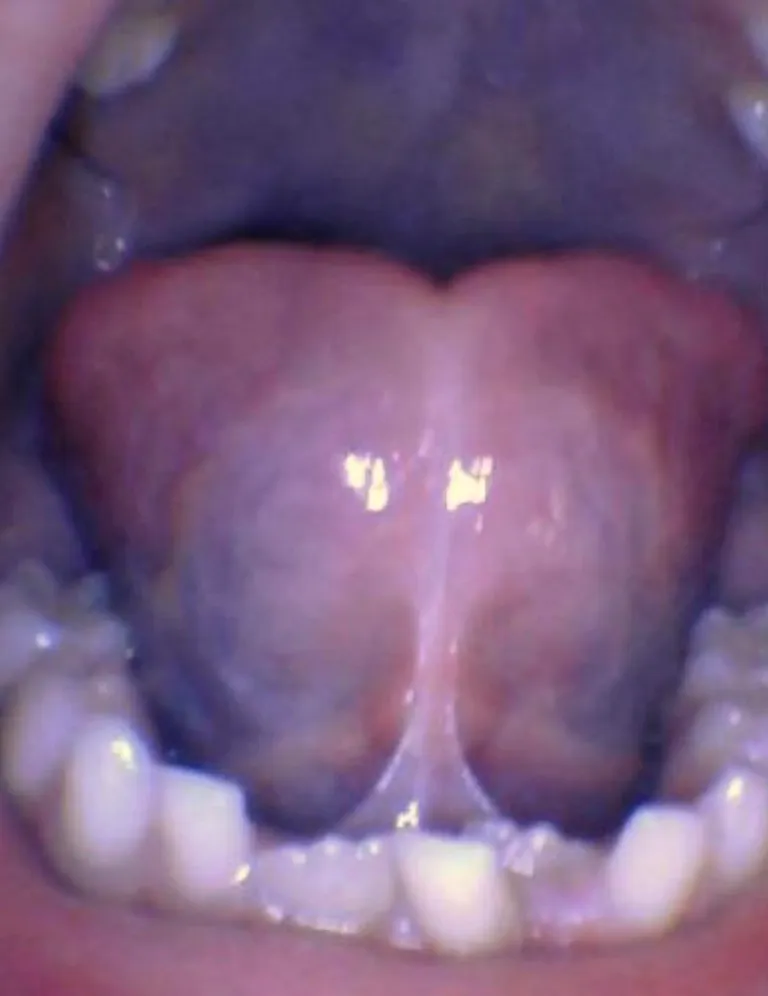

Un frein de langue restrictif est un « reste de tissu situé sur la ligne médiane entre la surface inférieure de la langue et le plancher buccal qui restreint le mouvement lingual physiologique » (IATP, International Affiliation of Tongue-Tie Professionals). Lorsqu'il est trop épais, trop serré ou trop court, il peut alors entraîner un ou plusieurs problèmes d'ordre fonctionnel (allaitement, ventilation, sommeil, dentition, parole, alimentation).

Il existe des spectres de restriction (site Tongue-Tie Alabama du Dr R. Baxter, Spectrum of lip/tongue restriction in infant/children), il n'existe pas une seule apparence. Il est donc important de comprendre la notion de symptomatique versus asymptomatique : un frein qui semble court ne sera opéré que s'il impacte la bonne fonction linguale, labiale ou jugale.

Photos ci-dessous issues du site Tongue-Tie Alabama avec l'accord de R. Baxter.

Bébé - Spectre de restrictions d'un FR lingual

Enfant - Spectre de restrictions d'un FR lingual